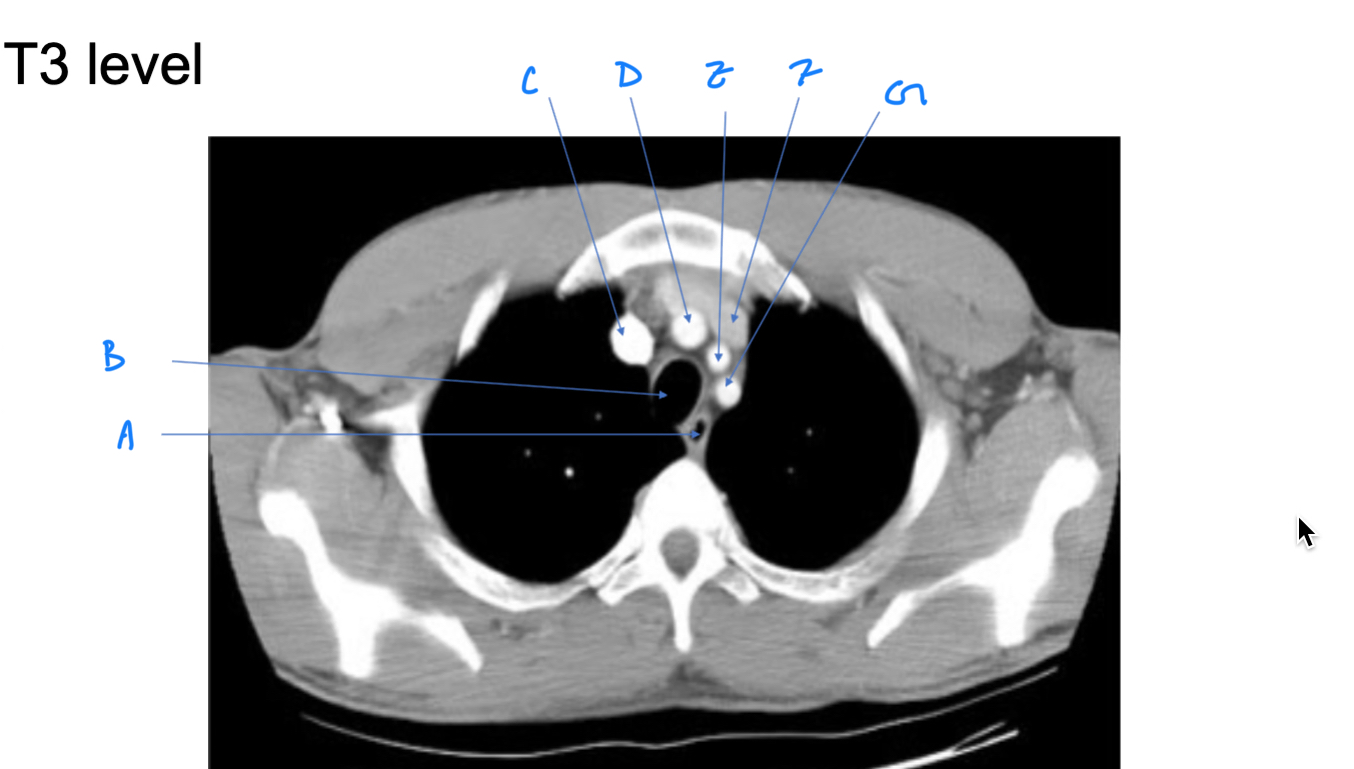

Esophagus

A. Identify

Trachea

B. Identify

R Brachiocephalic v.

C. Identify

Brachiocephalic trunk

D. Identify

L CCA

E. Identify

L Brachiocephalic v.

F. Identify

L Subclavian a.

G. Identify